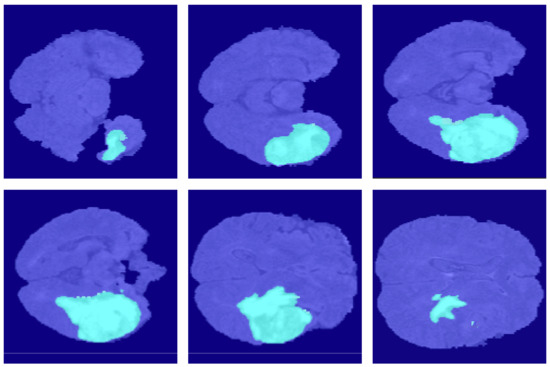

4.2. Segmentation Results

5.6.2. Third Dimensional Information Loss